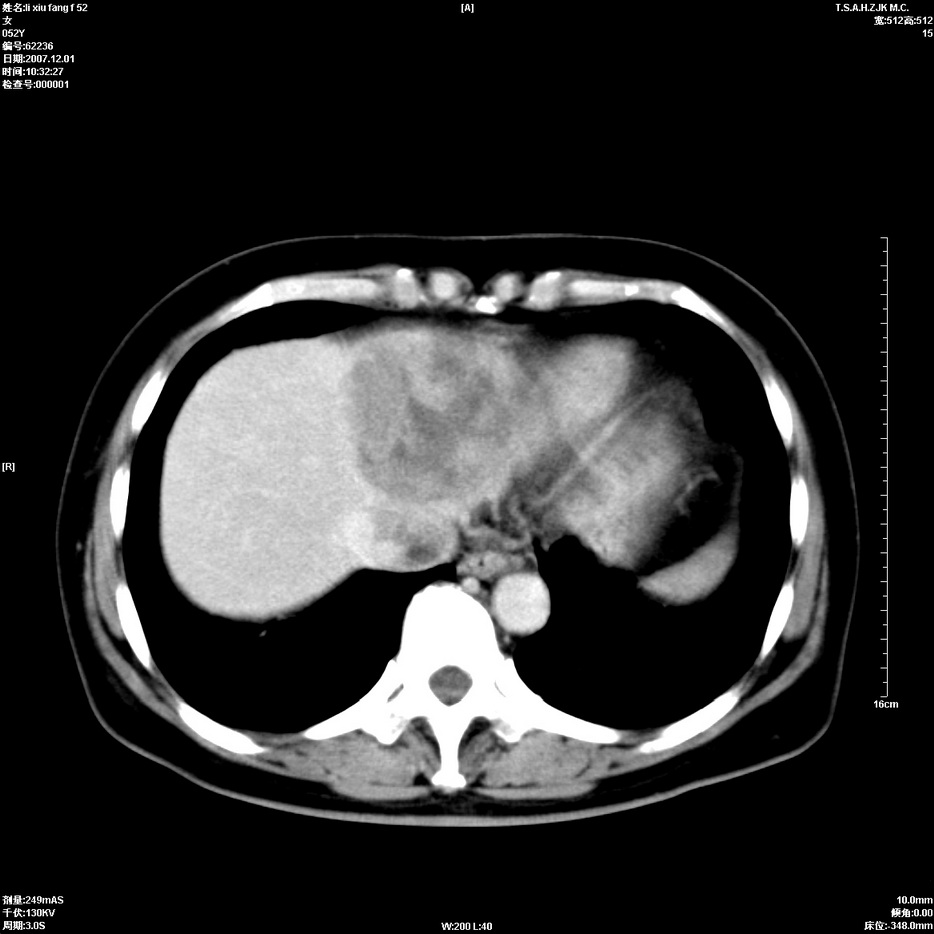

标题: CT12858:女,52岁,胎甲球蛋白861肝左叶占位,肝癌。下腔静 [打印本页]

标题: CT12858:女,52岁,胎甲球蛋白861肝左叶占位,肝癌。下腔静

肝左叶巨大低密度灶肿块,增强符合快进快出表现,有动静脉交通支;静脉期,下腔静脉内有充盈缺损,afp明显升高,支持肝癌并下腔静脉癌栓形成。

以下是引用拾荒者在2008-4-15 22:57:00的发言:[br]肝左叶巨大低密度灶肿块,增强符合快进快出表现,有动静脉交通支;静脉期,下腔静脉内有充盈缺损,afp明显升高,支持肝癌并下腔静脉癌栓形成。